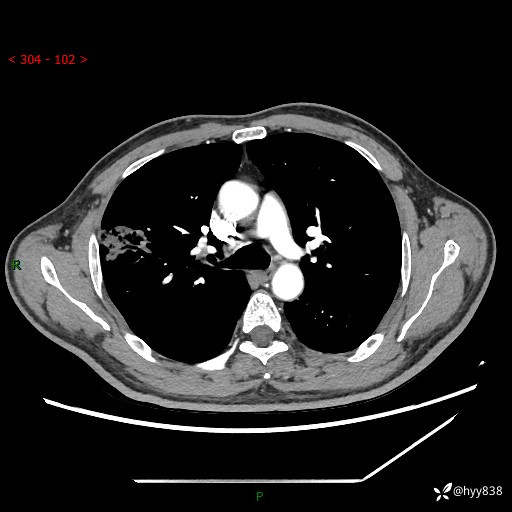

现病史:患者2天前体检完善胸部CT提示:右上肺团块影,炎症可能,肿瘤性病变不除外,冠状动脉钙化,无咳嗽、咳痰,无寒战发热,无恶心、呕吐等其他特殊不适,未予以特殊治疗,现为明确病变性质来我院就诊,门诊以“肺肿物性质待查”收入我科。 起病以来,患者精神、饮食、睡眠可,大小便正常,体力体重较前无明显变化。

胸部CT平扫+增强